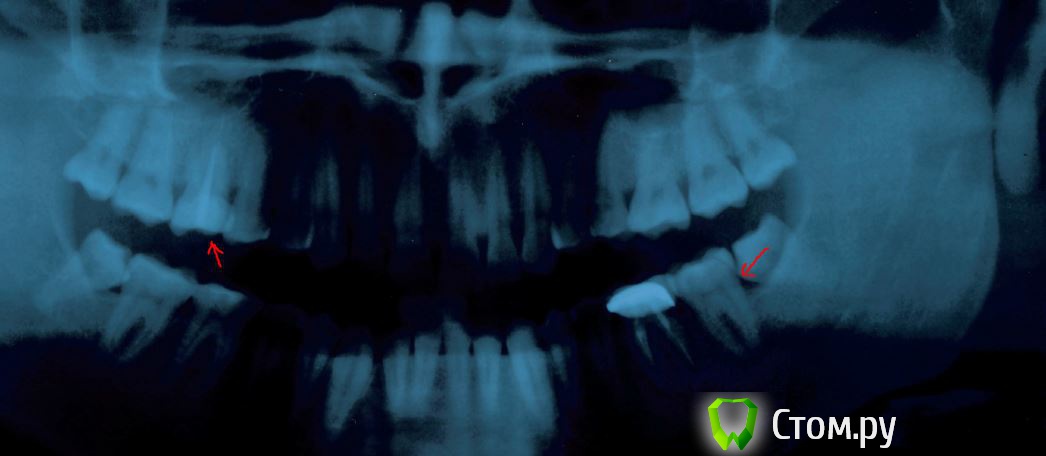

g_kot Опубликовано 31 мая, 2014 Автор Поделиться Опубликовано 31 мая, 2014 (изменено) Добрый всем день. Сделал КТ. Ваше мнение. Мне говорят про открытый синус. Закрытым не обойтись? А на втором снимке кариес? Изменено 31 мая, 2014 пользователем g_kot Ссылка на комментарий

g_kot Опубликовано 31 мая, 2014 Автор Поделиться Опубликовано 31 мая, 2014 Спасибо. Еще раз поговорю про это со своим доктором. А что скажете про темное место между 7 и 8 на втором снимке. Кариес??? или такая форма зуба возможна? Ссылка на комментарий

faity Опубликовано 31 мая, 2014 Поделиться Опубликовано 31 мая, 2014 Спасибо. Еще раз поговорю про это со своим доктором. А что скажете про темное место между 7 и 8 на втором снимке. Кариес??? или такая форма зуба возможна?я бы 8-ой удалил, 7 смотреть надо после удаления, скорее всего кариес Ссылка на комментарий

g_kot Опубликовано 1 июня, 2014 Автор Поделиться Опубликовано 1 июня, 2014 (изменено) Записался к врачу... А кариес в таком месте нормально можно залечить (после удаления 8ки) или он там слишком близко к корню? Изменено 1 июня, 2014 пользователем g_kot Ссылка на комментарий

red_butler Опубликовано 1 июня, 2014 Поделиться Опубликовано 1 июня, 2014 Записался к врачу... А кариес в таком месте нормально можно залечить (после удаления 8ки) или он там слишком близко к корню?Через две три недели после удаления "восьмерки" займетесть лечением кариеса, если судить только по снимку - все вполне лечибельно Ссылка на комментарий